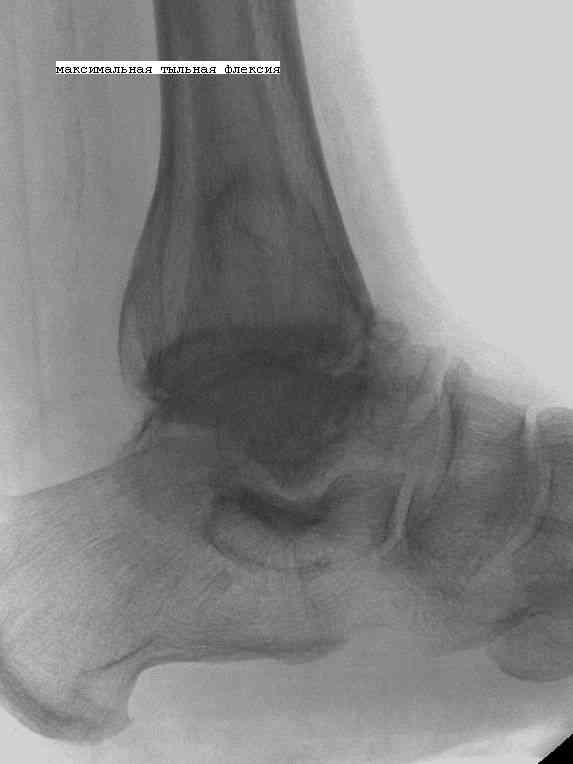

Эндопротезирование или артродезирование ?К нам обратился пациент 73 лет с жалобами на боли и деформацию в области левого голеностопного сустава. В анамнезе: в 1980 году перелом обеих лодыжек с вывихом стопы кнаружи. Лечился консервативно: одномоментная репозиция переломовывиха в левом голеностопном суставе с трансартикулярной фиксацией голеностопного сустава спицами Киршнера через пяточную, таранную, большеберцовую кости. Накладывалась гипсовая иммобилизация. Даная манипуляция осложнилась нагноением с развитием гнойного артрита. Были удалены спицы, сустав со слов больного, промывался растворами, но не вскрывался, получал антибиотики. Гнойный процесс был купирован, и рецидива с тех пор не было.Об-но: Левый голеностопный сустав деформирован за счет разрастания костной ткани и отечности мягких тканей. Левая стопа с вальгусной установкой, практически отсутствуют все своды левой стопы (стопа плоская). Полный объем движений в левом голеностопном суставе максимум достигает 15 гр, движения стопы в основном за счет подтарнного сустава. Пальпаторно область голеностопного сустава не столь болезненна, как болезненна область подтаранного сустава и область таранно-ладьевидного сустава.После изучения объективного статуса, анамнеза, рентгенснимков, больному предложен был трехсуставной артродез, так-как мы сочли это наиболее приемлемым в данном случае. Но больной отказывается от данной операции и настаивает на эндопротезировании левого голеностопного сустава. Во первых, наше отделение не имеет опыта в эндопротезиовании голеностопного сустава. Во вторых, нам кажется, что трехсуставное артродезирование в данном случае наиболее подходящее. Причиной тому, на наш взгляд, выраженная деформация левой таранной кости, как следствие аваскулярного некроза, и то что болит не голеностопный сустав в данном случае ( хотя в нем и ограничено движение), а подтранный и таранно-ладьевидный суставы и то что эндопротезирование одного голеностопного сустава не решит проблем в подтаранном, ладьевидно-таранном сочленениях. Наши доводы оказались безуспешными, а так как пациент является ученным, требовал доказательной базы наших умозаключений. Ваше мнение по данному случаю, и мы были бы благодарны, если у кого то есть материал по данной теме или есть ссылки. Заранее благодарны всем, кто примет участие в обсуждении данной темы.

По всем канонах хирургии стопы асептический некроз таранной кости - абсолютное противопоказание для эндопротезирования голеностопного сустава.